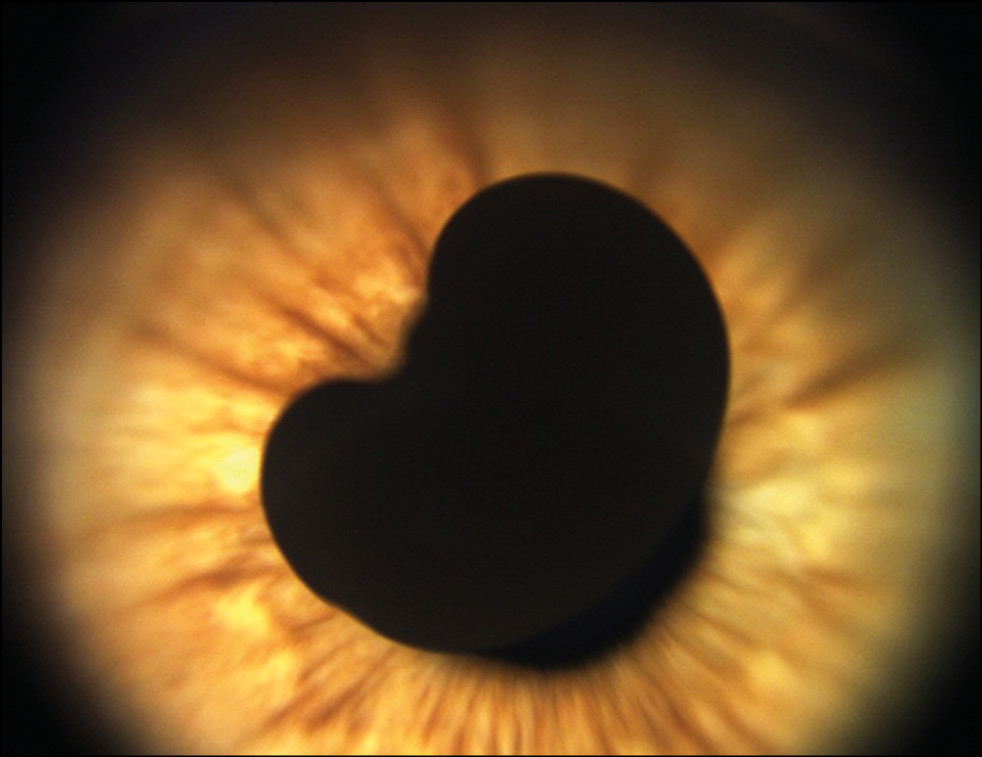

Пациентка Х., 4 года. Впервые заметили пигментное новообразование на радужке в 1 год на плановом осмотре по месту жительства. За последние 7 месяцев мама отметила рост новообразования, поэтому обратилась в Центр. Острота зрения составила 1,0. По результатам ультразвуковой биомикроскопии правого глаза отмечено в наружном отделе образование радужки размером 2,4×2,8×3,2 мм. Обследовано было затруднено в связи с маленьким возрастом ребёнка. Ребёнок был госпитализирован и обследован под общим наркозом. В результате комплексного обследования (ультразвукового исследования и Ret Cam) с учётом клинической картины было диагностировано пигментное новообразование радужки в области зрачкового края с выраженными приводящими сосудами. Отмечалось распыление пигмента по всей радужке и УПК в наружных и нижних отделах (рис. 7).

Рис. 7. Меланоцитома радужки.

По данным оптической когерентной томографии правого глаза отмечена гиперрефлективная поверхность образования с эффектом «тени» подлежащих структур (рис. 8).

Рис. 8. Оптическая когерентная томография радужки OD. Гиперрефлективная поверхность образования.

Проведена операция иридэктомия с иридопластикой правого глаза. Гистологическая картина соответствовала диагнозу меланоцитомы радужки. Пациентке рекомендовано динамическое наблюдение.